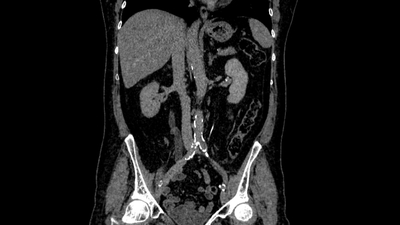

Наиболее информативное КТ с контрастированием: показывает степень расширения, уровень обструкции, функцию почек.